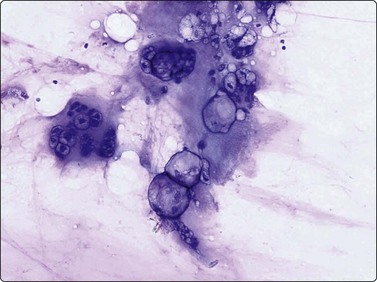

The pseudosarcomatous lesions are an important target for needling in this histogenetic group of tumors/lesions. Nodular fasciitis is among the commonest and the most frequently needled. Dahl and Åkerman reported 13 cases with cytology 1981;12 at present, our material comprises more than 70 cases, all with remarkably similar cytomorphology. In more recent investigations of the cytological features of nodular fasciitis, the results are similar to those of Åkerman and Dahl.13,14 The most important feature is the pleomorphism of the proliferating fibroblasts/myofibroblasts. Nuclei are predominantly spindly, but a proportion of cells have plump, ovoid or kidney-shaped nuclei. Bi-and/or multinucleated forms are always present and, if looked for carefully, ganglion cell-like binucleate cells with triangular shape and eccentrically placed nuclei are found (Fig. 15.1). A high cell content, nuclear pleomorphism, prominent nucleoli and the presence of mitoses may suggest malignancy, but the pale, bland nuclear chromatin is a clear indication of the benign nature of the lesion (Fig. 15.2). The correct diagnosis depends on the clinical presentation and the anatomical site (a rapidly, often tender subcutaneous nodule most frequently appearing in the upper extremity, trunk, head and neck) combined with such cytologic features as a myxoid background, actively proliferating fibroblasts/myofibroblasts and the presence of inflammatory cells.

image

Fig. 15.1 Nodular fasciitis

Proliferating fibroblasts embedded in a myxoid background; note binucleate cell with abundant cytoplasm and eccentric nuclei (ganglion cell-like) (MGG, HP).